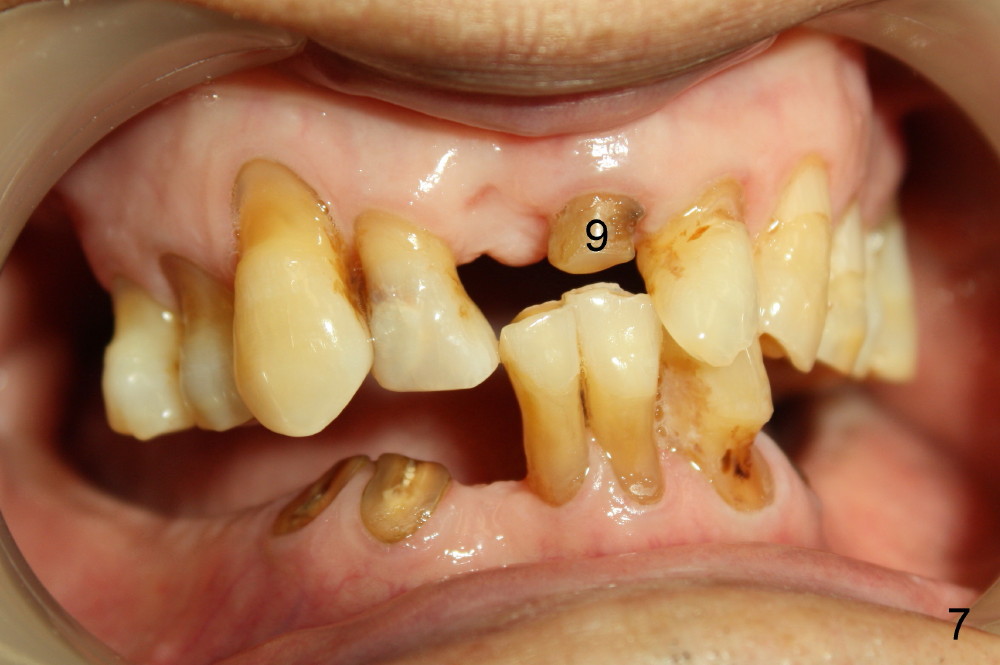

Buccal atrophy at the site of #8 dictates a smaller implant than that of #9 (Fig.4-7).